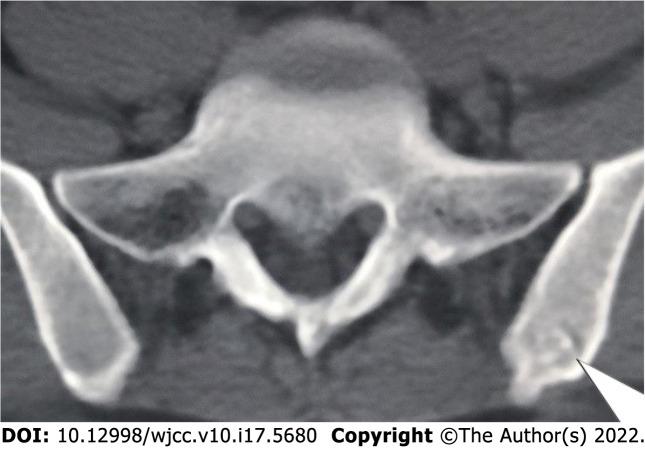

We designed a new anatomic hook-rod-pedicle screw system for young patients with lumbar spondylolysis. The isthmus and the corresponding pedicle screw entry point were exposed through the intermuscular approach. Autogenous iliac bone graft was obtained to bridge the isthmus defect, and then the anatomic hook-rod-pedicle screw system was used to fix the isthmus in 15 young patients.

At 24 mo follow-up, the visual analogue scale score of low back pain decreased from 6.73 ± 0.88 to 0.73 ± 0.59, and the Oswestry disability index score decreased from 58.20 ± 8.99 to 7.87 ± 4.97. Computed tomography showed bilateral isthmic bone healing in 14 cases and unilateral isthmic bone healing in 1 case. Magnetic resonance imaging showed that the lumbar disc signal of diseased segment and adjacent segments had no change compared with that before surgery. The pain visual analogue scale score of the donor site was 0.20 ± 0.41 at the last follow-up. According to the Modified Macnab score, the excellent and good rate was 100%.

方法

随访24个月时,腰痛视觉模拟评分从6.73±0.88降至0.73±0.59,Oswestry功能障碍指数评分从58.20±8.99降至7.87±4.97。CT显示14例双侧峡部骨愈合,1例单侧峡部骨愈合。MRI显示病变节段及相邻节段腰椎间盘信号与术前相比无变化。末次随访时供区疼痛视觉模拟评分为0.20±0.41。根据改良Macnab评分,优良率为100%。